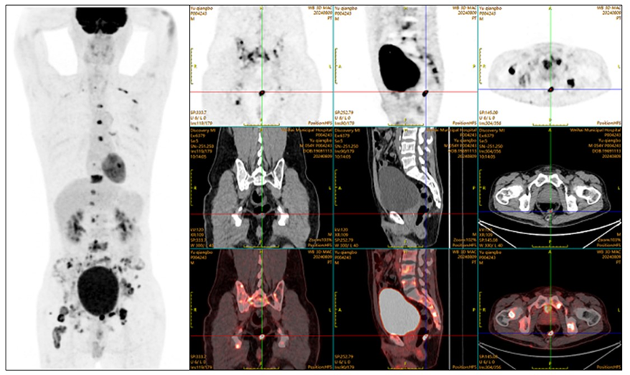

病例(2)為一中年男性,因右下肢疼痛、麻木就診,外院MRI提示胸腰骶椎、骨盆多發(fā)異常信號;18F-FDG PET/CT示直腸軟組織密度結(jié)節(jié)伴代謝增高,全身骨多發(fā)代謝增高灶,部分伴溶骨性骨質(zhì)破壞;患者行腸鏡檢查示直腸粘膜下隆起病變,活檢病理提示直腸上皮樣血管肉瘤,臨床診斷直腸上皮樣血管肉瘤合并多發(fā)骨轉(zhuǎn)移可能大。